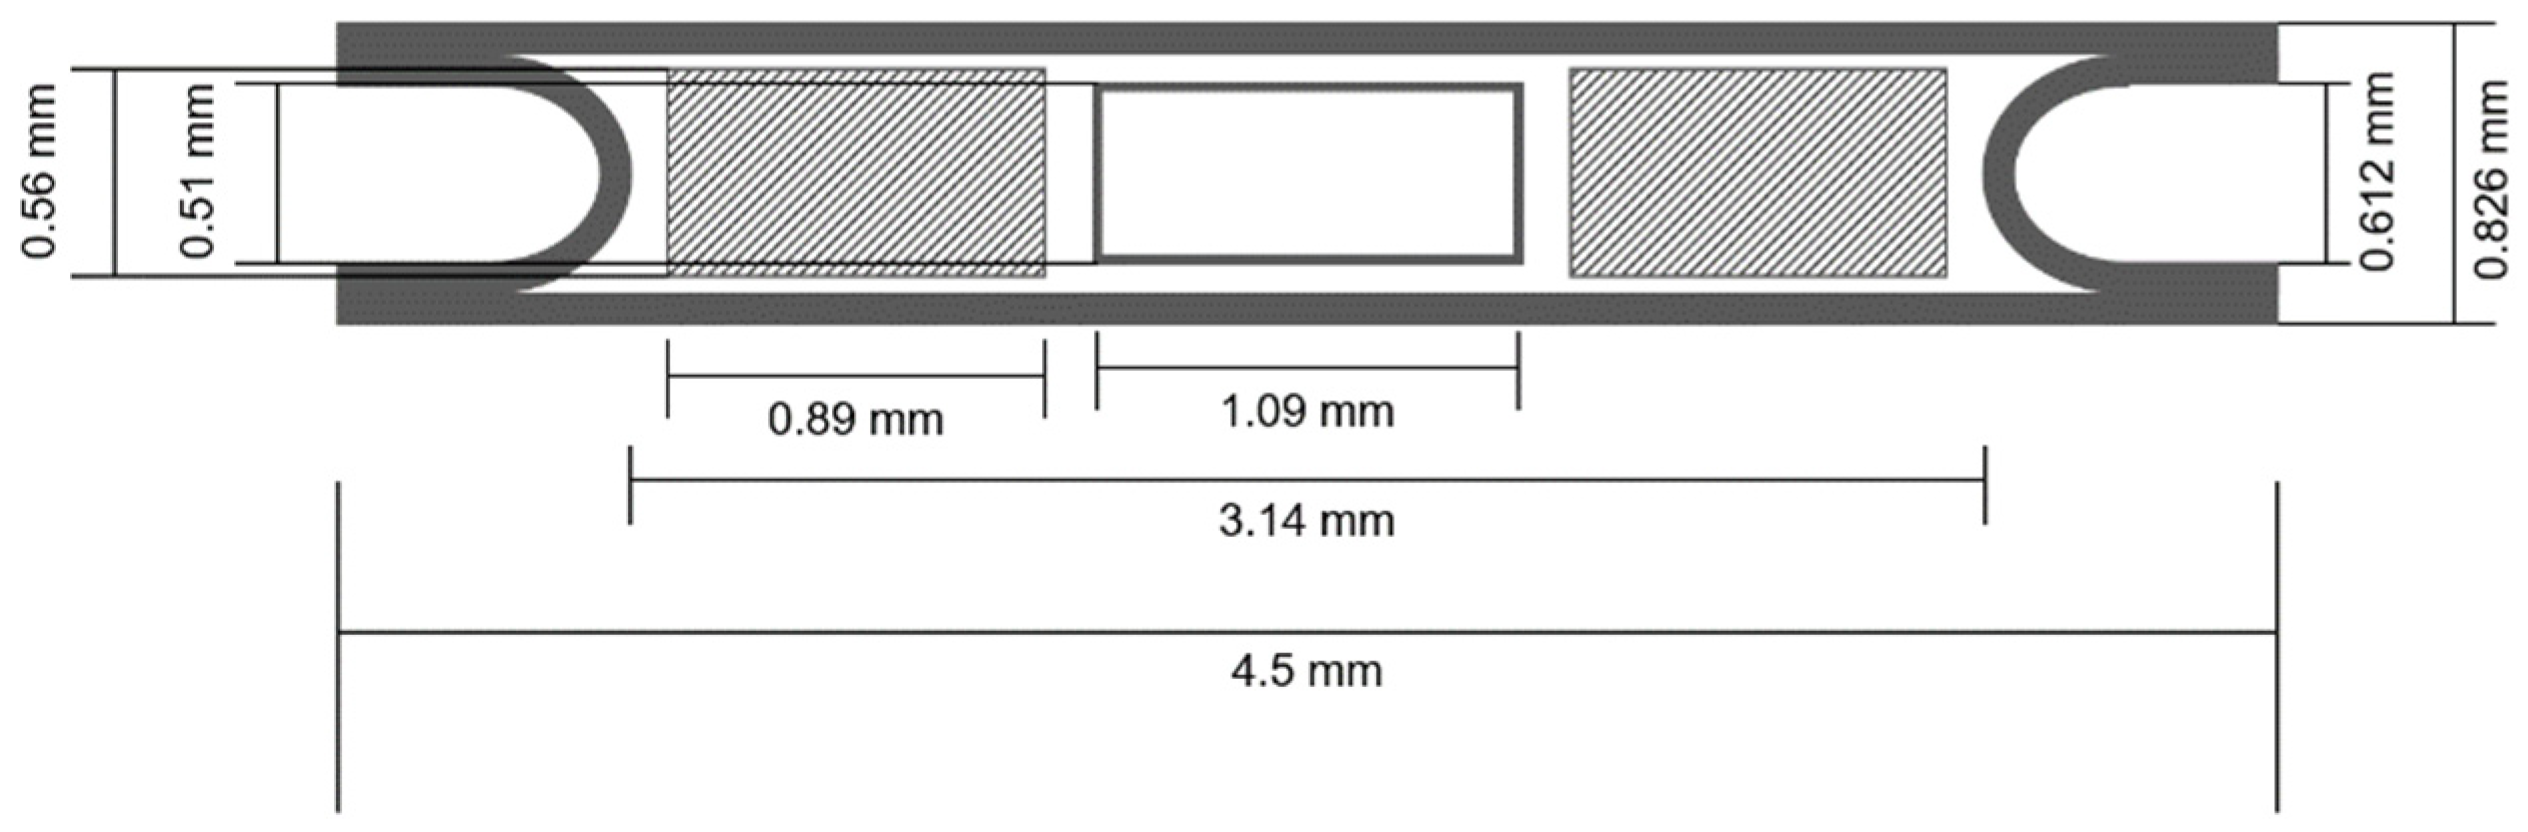

2.3. Brachytherapy Seed Simulations

3.2. Radioactive Magnetic Nanoparticle (RMNP) Seed